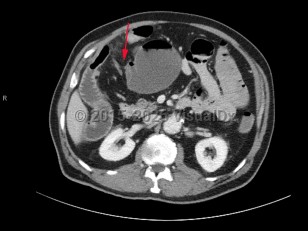

A small bowel obstruction (SBO) occurs when intraluminal bowel contents fail to pass through the small intestine. Impaired passage of bowel contents results in dilation of the proximal bowel, with fluid accumulation, gas production, increased intraluminal pressure, and bacterial overgrowth. This results in abdominal distension and pain, nausea, and vomiting, with risk of bowel ischemia and perforation.

SBOs can be classified as partial or complete. Partial SBOs permit some passage of bowel contents past the obstruction site, while complete SBOs are associated with the inability to pass any gas or fluid past the obstruction. Partial SBOs can further be stratified into high-grade or low-grade, depending on the severity of obstruction, with low-grade SBOs presenting with less severe symptoms. A simple SBO is characterized by a single point of obstruction. A closed-loop obstruction is characterized by occlusion of the bowel at 2 points and has the highest risk of ischemia due to occlusion of the blood supply.